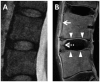

Tissues, such as bone, tendon, and ligaments, contain a high fraction of components with "short" and "ultrashort" transverse relaxation times and therefore have short mean transverse relaxation times. With conventional magnetic resonance imaging (MRI) sequences that employ relatively long echo times (TEs), there is no opportunity to encode the decaying signal of short and ultrashort T2 /T2 * tissues before it has reached zero or near zero. The clinically compatible ultrashort TE (UTE) sequence has been increasingly used to study the musculoskeletal system. This article reviews the UTE sequence as well as various modifications that have been implemented since its introduction. These modifications have been used to improve efficiency or contrast as well as provide quantitative analysis. This article reviews several clinical musculoskeletal applications of UTE.